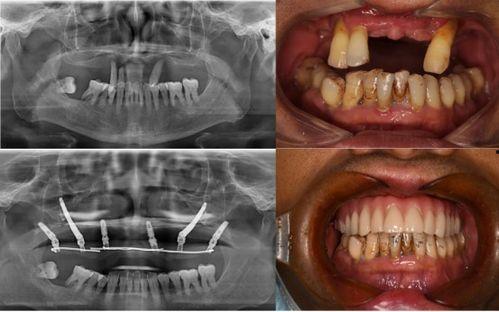

对于这起事件,口腔医学专家表示,种植牙作为一种常见的牙齿修复方式,确实存在一定的风险。虽然种植牙的成功率较高,但术后并发症也是不可避免的。

专家指出,种植牙术后可能会出现疼痛、感染、松动等问题。这主要是因为手术过程中,医生的技术水平、手术器械的消毒程度以及术后护理等因素都会影响到种植牙的成功率。